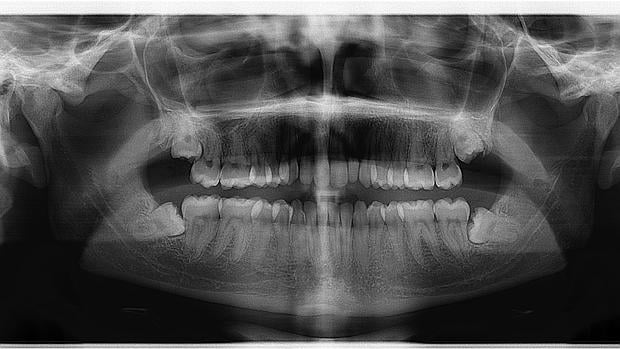

Solución

El periodoncista elimina la infección mediante un limpiado profundo de las encías justo hasta la misma raíz de los dientes y propone unos cuidados en casa y seguimiento periódico para evitar que vuelva a aparecer la enfermedad.